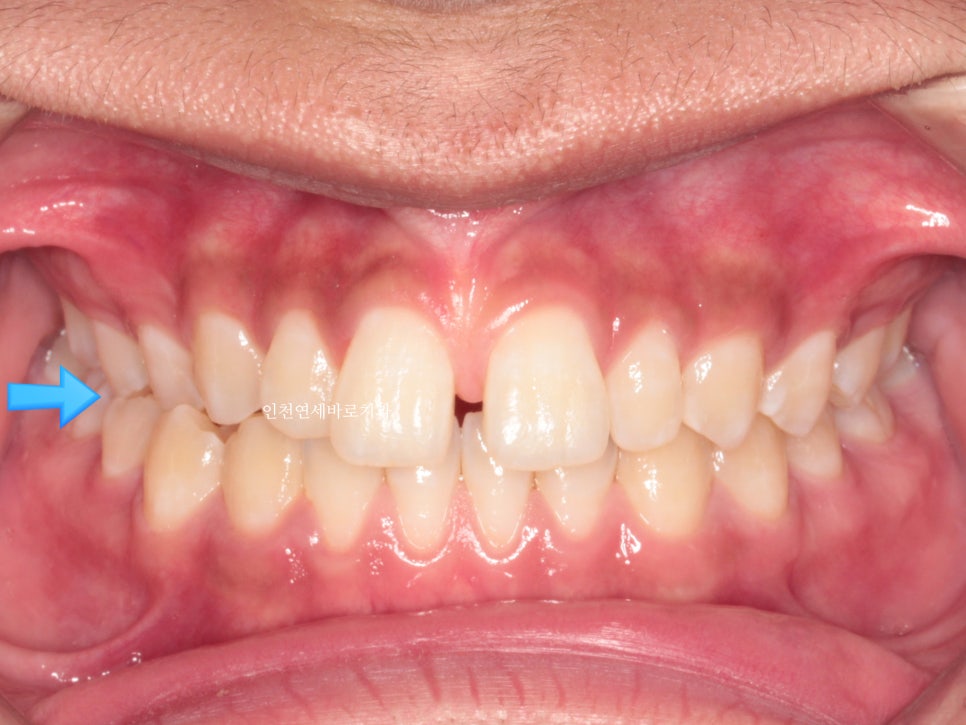

앞니가 벌어진 것도 문제였지만

화살표쪽에 보이는 반대교합도 문제였습니다.

문제가 되었던 오른쪽 어금니 교합도 좋게 마무리 하였습니다.